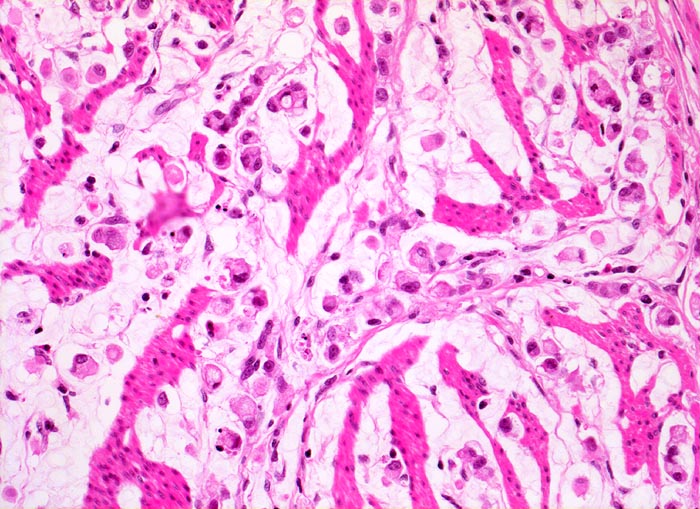

Adenokarzinom des Magens mit Siegelringzellen

Ein Grossteil des Tumorinfiltrats besteht aus einzeln liegenden Siegelringzellen mit intrazytoplasmatischen Schleimvakuolen. Zwischen den Tumorzellen liegen Reste der Magenwandmuskulatur.

Diffuse Verdickung und Versteifung der Magenwand im Sinne einer Linitis plastica bei intakter Schleimhautoberfläche. Aufhebung des Faltenreliefs.